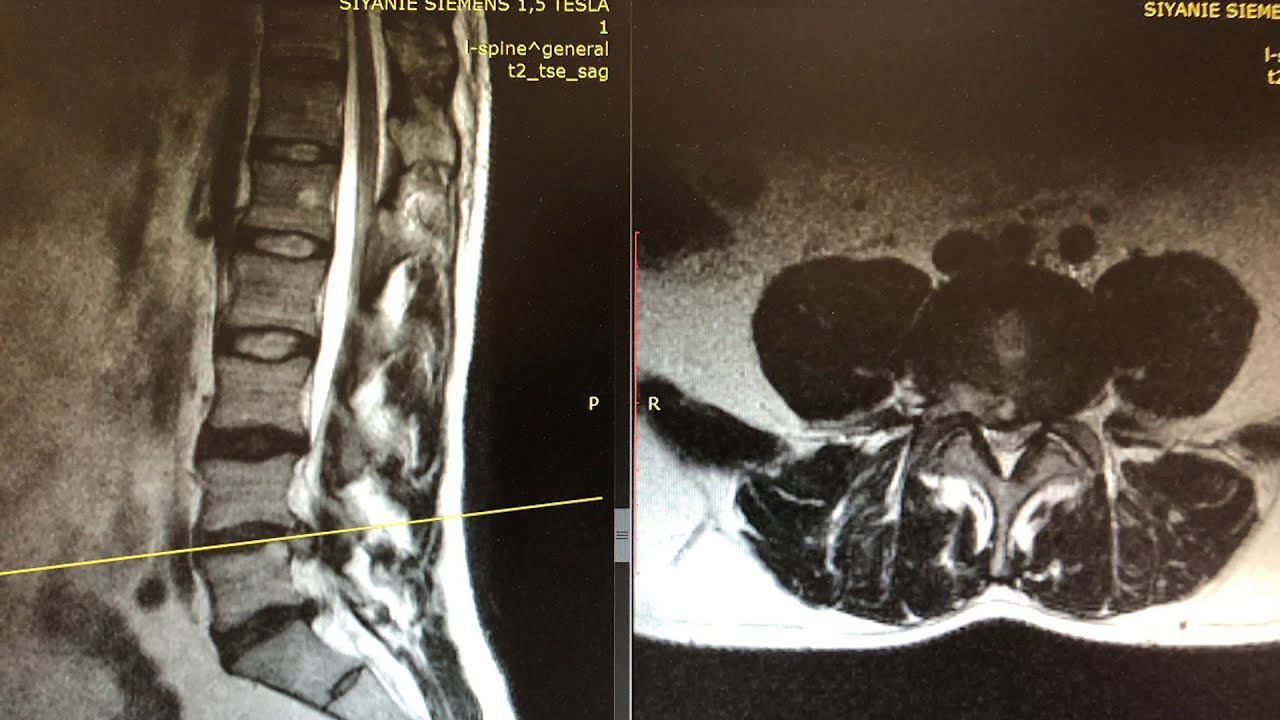

Диагноз l5 s1

Диагноз l5 s1 137 фото